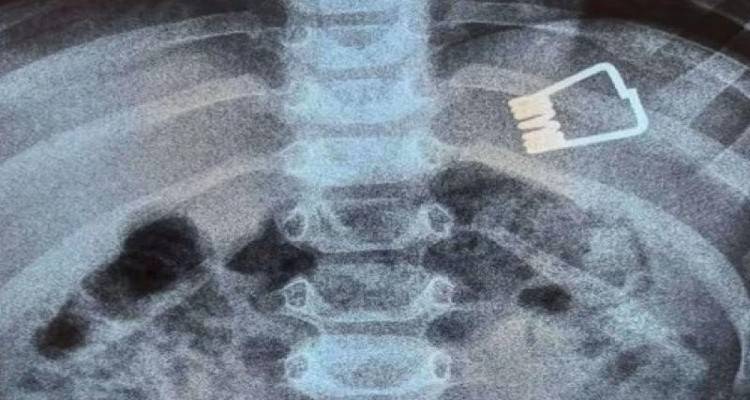

Μία συνηθισμένη ημέρα, μια οικογενειακή στιγμή έγινε ξαφνικά μία κούρσα αγωνίας .Λίγα δευτερόλεπτα ήταν υπεραρκετά για τον μικρό που εξερευνώντας το σπίτι του πρόλαβε να απλώσει το χέρι να ανοίξει το μανταλάκι και να καταπιεί το μεταλλικό έλασμά. Οι γιατροί δεν πίστευαν στα μάτια τους βλέποντας την ακτινογραφία.

Αγοράκι 22 μηνών κατάπιε έλασμα από μανταλάκι

«Έπαιζε με τα παιχνίδια του, κάποια στιγμή γιατί είχαμε την απλώστρα μέσα λόγω υγρασίας, λόγω είχε βροχές εκείνες τις ημέρες, άπλωσε το χέρι του και πήρε ένα μανταλάκι, το άνοιξε, το χάλασε και τώρα ακριβώς ποια στιγμή το κατάπιε, δεν ξέρω. Τον ακούσαμε λίγο που έβηξε και εκεί υποψιαστήκαμε ότι μπορεί να κατάπιε κάτι. Και τον πήραμε εμείς, πήρα την παιδίατρο βασικά τηλέφωνο και μου είπε να πάμε να βγάλουμε κατευθείαν ακτινογραφία. Το πήγαμε στο νοσοκομείο της Λήμνου. Τον βγάλαμε ακτινογραφία. To είδαμε ότι είναι στο στομαχάκι του. Έκανε το παιδί rapid test και η μάνα του για να μπορούν να μπούνε μέσα το βράδυ.», λέει συγκλονισμένος ο πατέρας του δίχρονου.